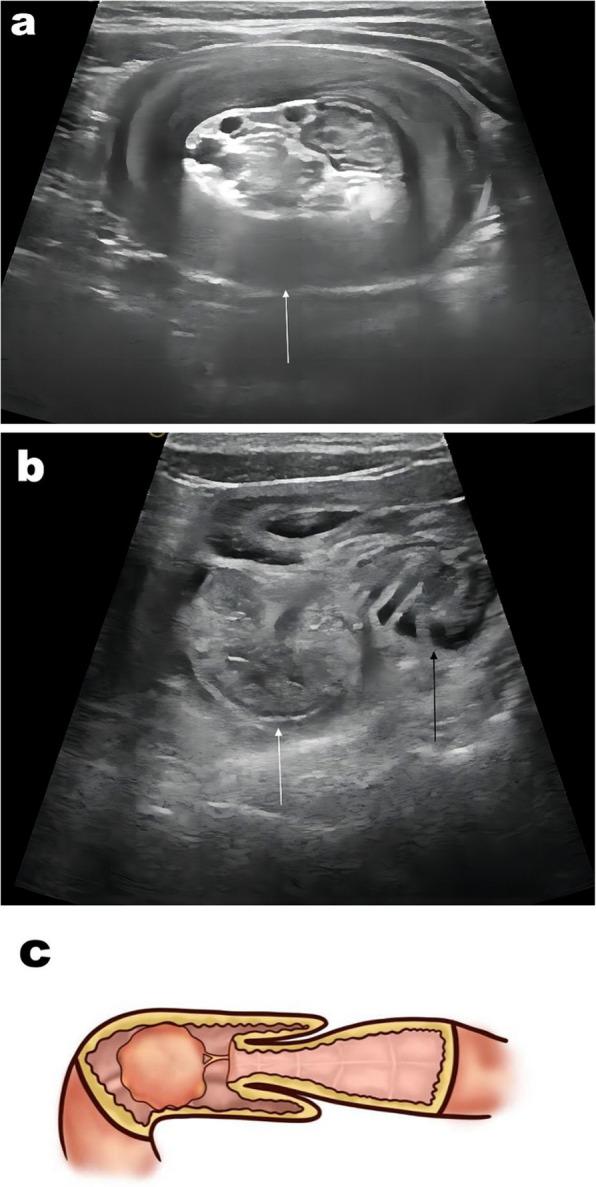

From February 2019 to June 2022, ultrasound (US) features and clinical findings of pediatric patients with small-bowel intussusception (SBI)-including SBI diameter, outer bowel wall thickness, thickness of the head and body of the intussusceptum, length of the intussusceptum, and presence of pathological lead points (PLPs)-were recorded and analyzed. A classification and regression tree algorithm was then used to develop a DTA model, which was trained and validated by randomly categorizing the patients into training (60%, 200/331) and validation (40%, 131/331) datasets to assess diagnostic performance.

A total of 331 patients with SBI (270 with TSBI and 61 with PSBI) were included; the maximum age was 9 years. The initial diagnostic predictor in the DTA model was the detection of a PLP via US, followed by intussusceptum length (P < 0.001). The sensitivity, specificity, and accuracy of the DTA model were 98.2%, 100%, and 98.6%, respectively.